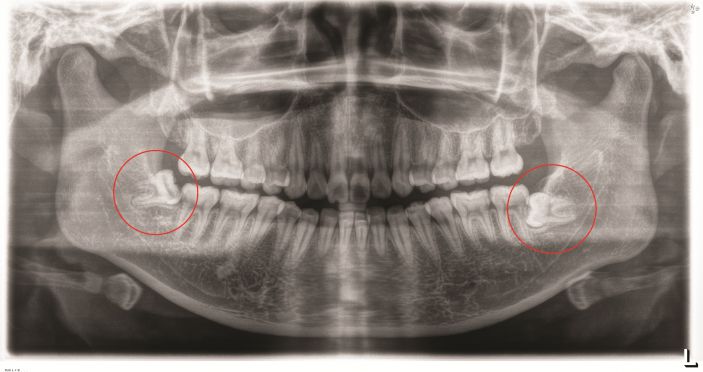

△智牙拔除後。